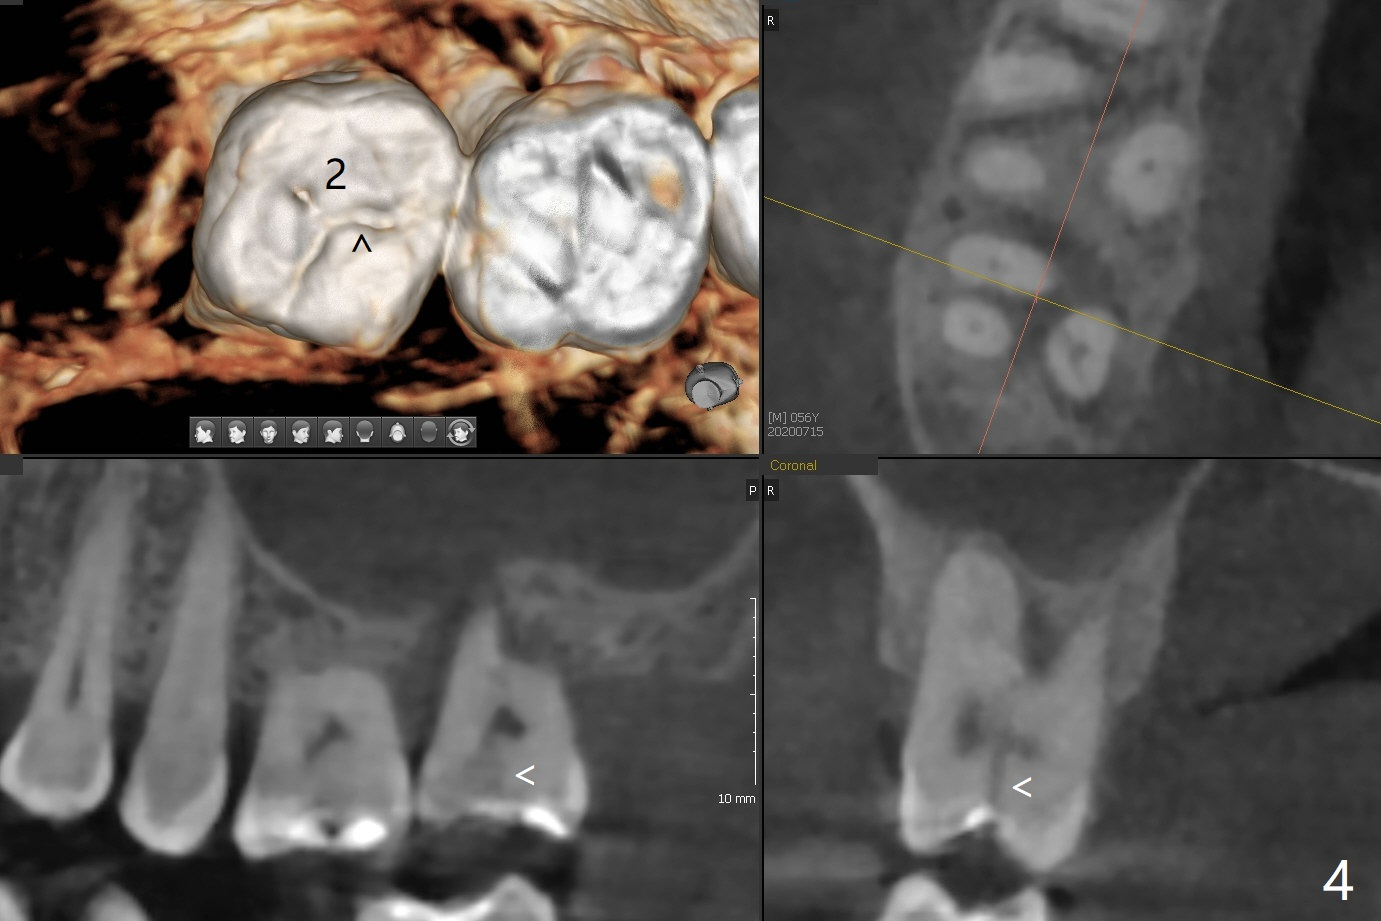

A 56-year-old man (smoker) has pain at #2 (Fig.1-3 thickened sinus membrane (R>L), C: mucous retention cyst) associated with subgingival crack (Fig.4 arrowheads). A 5x8.5 mm implant will be immediately placed with sinus lift aided by PRF membrane (Fig.5). A narrow implant will be placed at #30 (Fig.6).